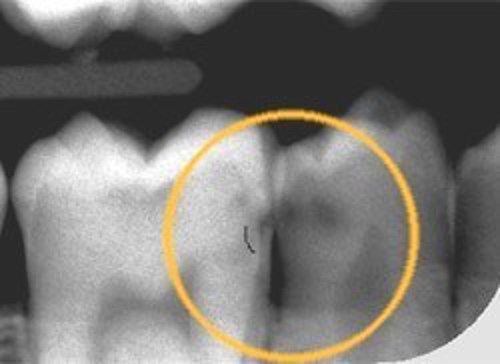

Huller mellem tænderne

Ofte dannes hullerne også mellem tænderne, hvor man ikke kan se dem med det blotte øje. Det kan derfor være nødvendigt, at tage røntgenbilleder af tænderne, for at opdage hullerne.

Andet røntgenbillede viser et stort hul. I cirklerne ses de små sorte pletter mellem tænderne, som er de begyndende huller.